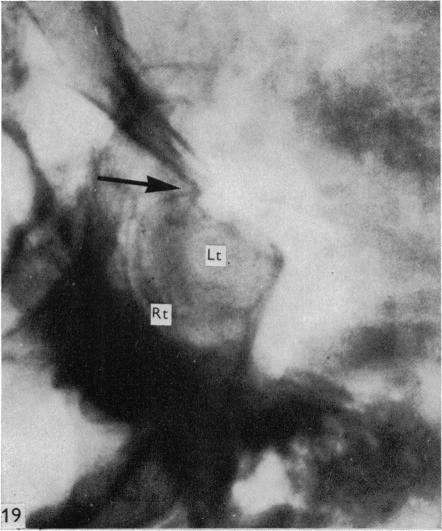

Surgical aspects of the anatomy of the sphenoidal sinuses and the sella turcica.

J Anat. 1977 Dec;124(Pt 3):541-53.